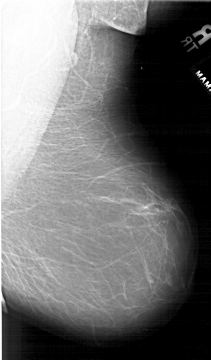

A_1902_1.RIGHT_MLO

RIGHT_MLO LINES 6106 PIXELS_PER_LINE 3571 BITS_PER_PIXEL 12 RESOLUTION 43.5 NON_OVERLAY